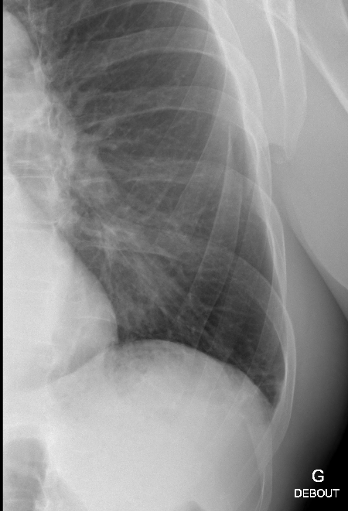

Nous retenons comme diagnostic une fracture de côte sur chute de sa hauteur sans pneumothorax associé.